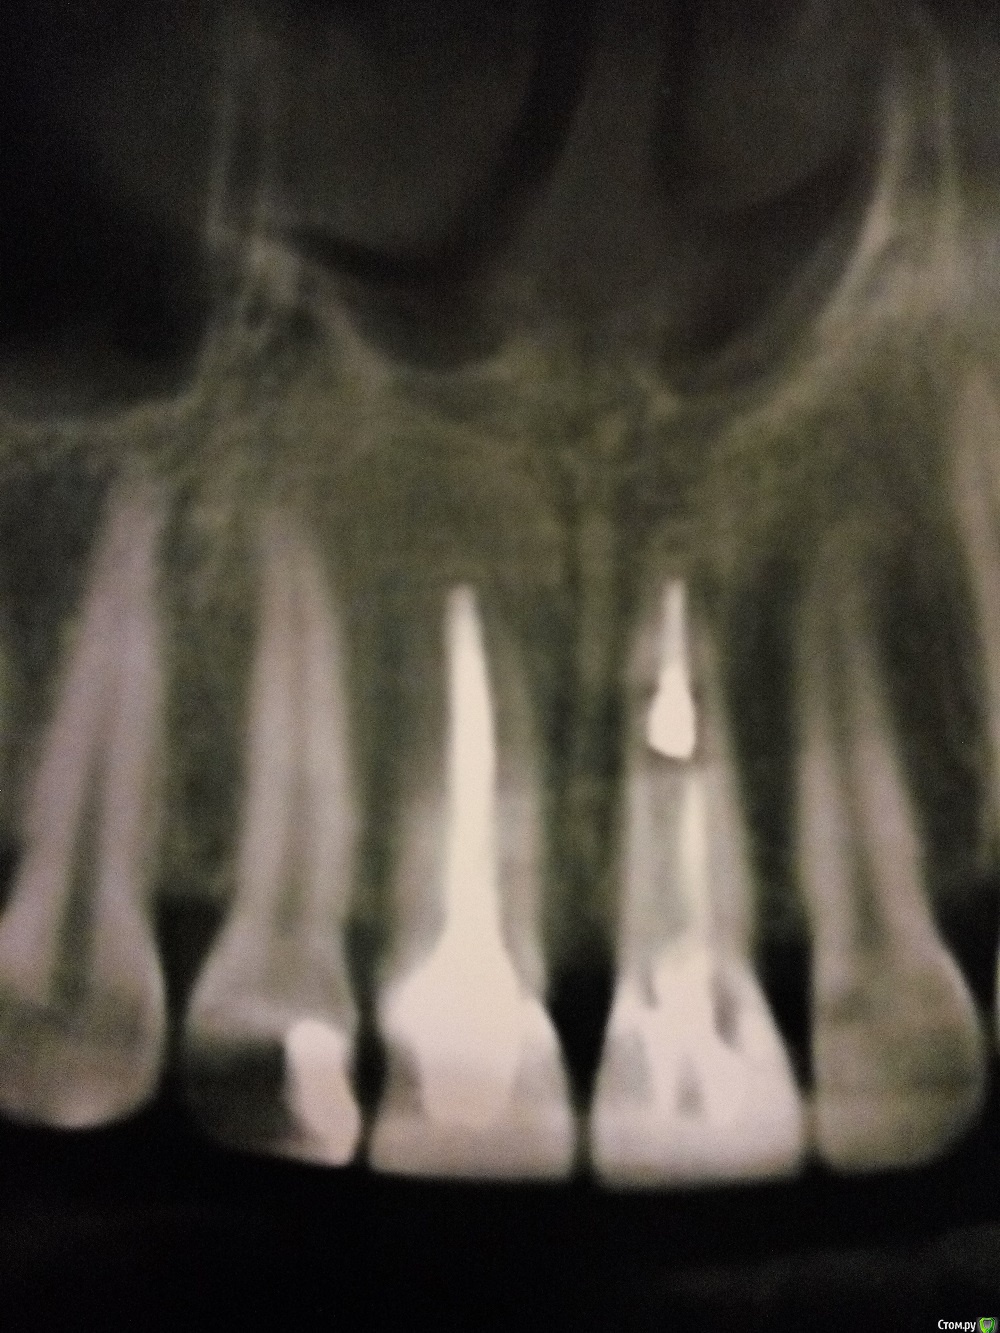

Opp80 Опубликовано 14 января, 2016 Автор Поделиться Опубликовано 14 января, 2016 (изменено) Сделал видео из КТ там видно уступ от старого штифта, хотя врач говорит апекс не пищал крови не былоhttps://yadi.sk/i/w9mc23axmyYuC только нажмите скачать , онлайн видео не проигрывает почему то, и снимок единиц отсканировал качество максимальное такой снимок Изменено 14 января, 2016 пользователем Opp80 Ссылка на комментарий

DmitrySH Опубликовано 14 января, 2016 Поделиться Опубликовано 14 января, 2016 Да, там очень тонко все, но признаков воспаления вокруг той зоны на кт не увидел 1 Ссылка на комментарий